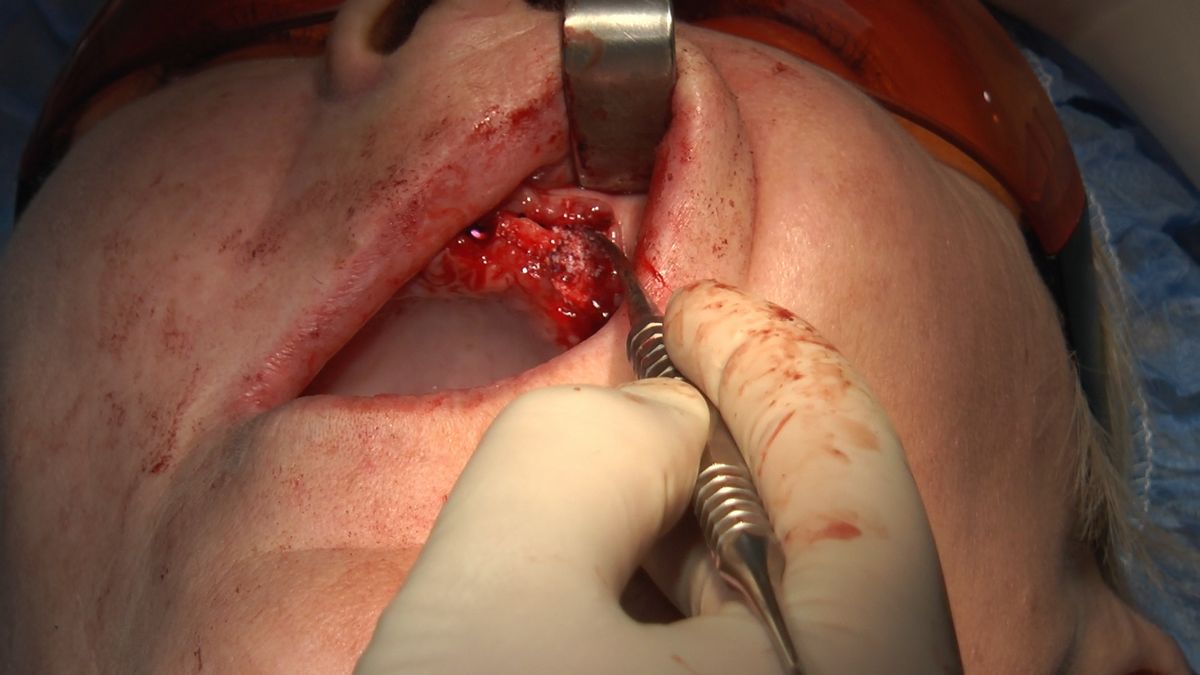

W ostatni weekend czerwca 2018 roku kursanci II Sezonu Preludium Implantologii odbyli piątą, finałową sesję, która w całości podporządkowana była praktyce. W ciągu dwóch dni zabiegowych Lekarze uczestniczący w szkoleniu przeprowadzili szereg zabiegów pod kierunkiem dr n.med. Violetty Szycik. Wszczepili 17 implantów oraz przeprowadzili ekstrakcje i zabiegi regeneracyjne kości. Zabiegi były wykonywane także w sedacji dożylnej z udziałem specjalisty anestezjologii i intensywnej terapii dr Jolanty Grzybowskiej. Preludium implantologii to nowy program edukacyjny dla adeptów implantologii stomatologicznej, którego celem jest wprowadzenie do implantologii poprzez pozyskanie wiedzy w szerokim zakresie i uwzględnieniem szczegółów mających decydujące znaczenie dla powodzenia leczenia implantologicznego. Ale tak jak wszystkie szkolenia w Instytucie Vivadental, w tym wiodące Practiculum Implantologii, zorientowane jest na praktyce i samodzielnym wykonywaniu zabiegów pod kierunkiem Mentora. To najlepsza edukacja w medycynie zabiegowej, a zarazem najlepszy start do implantologii.